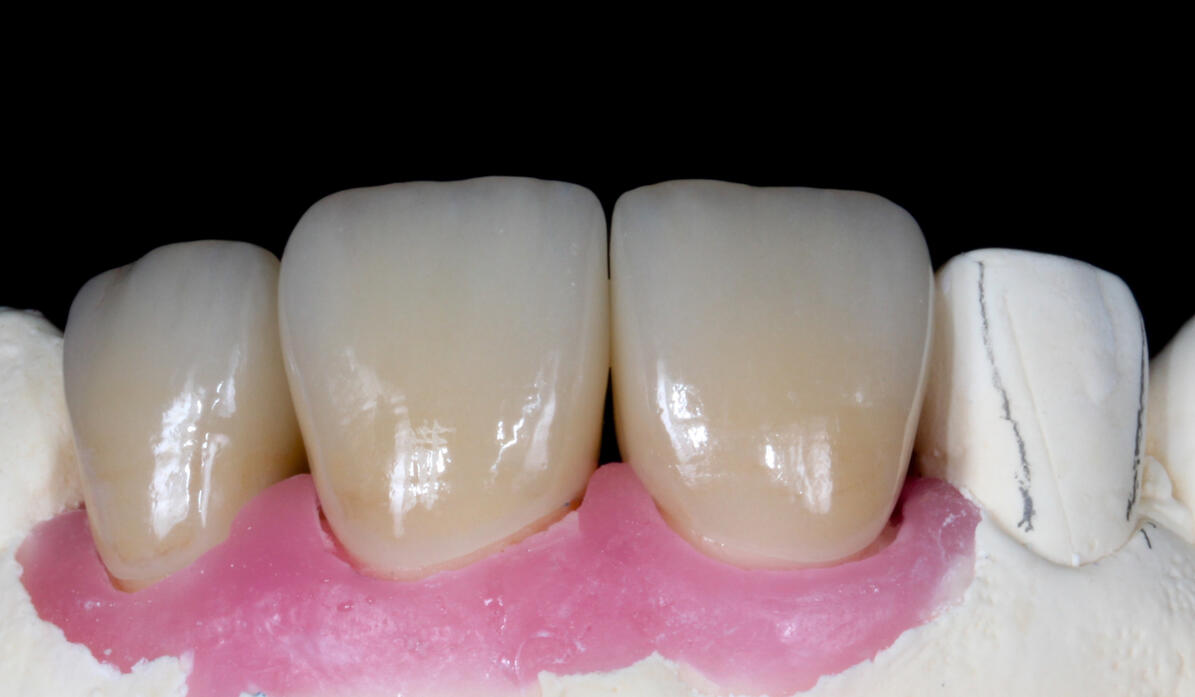

obecné zásady preparace pilířového zubu

základy plánování, volba materiálu a práce s ním od preparace po fixaci

základy estetického plánování

prezentace úspěšných i neúspěšných případů